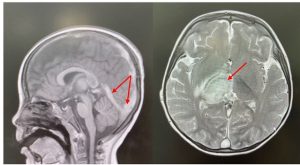

Hình ảnh huyết khối và tổn thương não trên phim MRI não của bệnh nhi. Ảnh: BVCC

Bé được chỉ định chụp CT scan sọ não cấp cứu, kết quả ghi nhận nhồi máu đồi thị (P) kèm phù não xung quanh, huyết khối lan toả tĩnh mạch vỏ não, xoang tĩnh mạch nội sọ, kéo dài đến tĩnh mạch cảnh chung (T), đường giữa lệch sang (T). Chụp cộng hưởng từ sọ não sau đó cũng ghi nhận hình ảnh nhồi máu kèm xuất huyết vùng đồi thị (P), vùng đính (P), lồi thể chai, chất trắng cạnh hai não thất bên, trung tâm bầu dục 2 bên và huyết khối tĩnh mạch nội sọ lan toả.